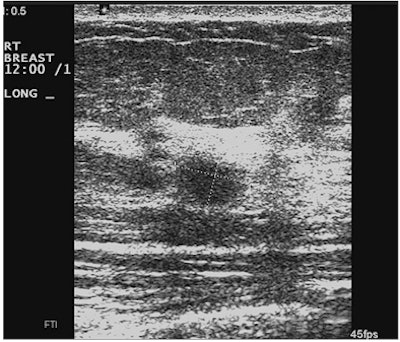

Real-time compound scanning combines the echoes obtained from multiple lines of sight at various angles of ultrasound exposure, compared with the single vertical beam in a standard linear-array transducer, in an attempt to improve the visibility of lesions. But is this technique necessary?

"Due to marketing efforts by some manufacturers, this type of image processing is now a default setting on most scanners sold in this country," Fornage said. "But evidence-based studies proving the superiority of this technique over standard sonography in the detection or characterization of breast lesions are still missing. In fact, the majority of breast ultrasound studies brought in from outside MD Anderson by patients referred to our institution have been performed with real-time spatial compounding and are at times useless because of the blurring affecting them."

Another drawback to this type of image processing is the disappearance of "good" artifacts, such as sound-through transmission, shadowing, and comet-tail artifacts, according to Fornage.

| Images show deterioration with the use of spatial compounding. Above, sonogram of a small carcinoma obtained with spatial compounding turned on. Below, sonogram of the same lesion obtained with conventional grayscale US settings without spatial compounding. |